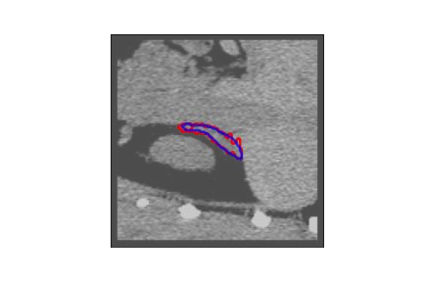

The human annotations are imperfect, especially when produced by junior practitioners. Multi-expert consensus is usually regarded as golden standard, while this annotation protocol is too expensive to implement in many real-world projects. In this study, we propose a method to refine human annotation, named Neural Annotation Refinement (NeAR). It is based on a learnable implicit function, which decodes a latent vector into represented shape. By integrating the appearance as an input of implicit functions, the appearance-aware NeAR fixes the annotation artefacts. Our method is demonstrated on the application of adrenal gland analysis. We first show that the NeAR can repair distorted golden standards on a public adrenal gland segmentation dataset. Besides, we develop a new Adrenal gLand ANalysis (ALAN) dataset with the proposed NeAR, where each case consists of a 3D shape of adrenal gland and its diagnosis label (normal vs. abnormal) assigned by experts. We show that models trained on the shapes repaired by the NeAR can diagnose adrenal glands better than the original ones. The ALAN dataset will be open-source, with 1,594 shapes for adrenal gland diagnosis, which serves as a new benchmark for medical shape analysis. Code and dataset are available at https://github.com/M3DV/NeAR.